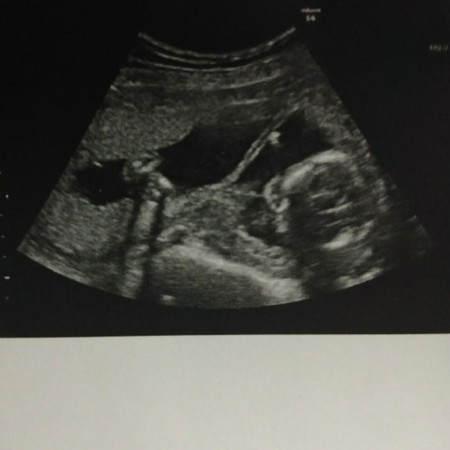

กังวลมากค่ะ

เพิ่งกลับจากหาหมอค่ะ หมอพบพังผืดในถุงน้ำคร่ำตามภาพเลยค่ะ คุณแม่คนไหนเคยเจอกับเคสแบบนี้บ้างคะ ตอนนี้เป็นกังวลมากๆเลยค่ะ

เคยอ่านบทความอยู่น่ะคะ ระดับความรุนแรงมันกว้างมาก คุณหมอบอกมั้ยคะ ว่ามันอยู่ตำแหน่งไหนบ้าง ถ้าผ่าตัดรักษาโอกาสที่น้องจะเสียชีวิตก็มีสูงค่ะ ต้องดูว่ามันไปรัดแขนรัดขาน้องมากแค่ไหนค่ะ